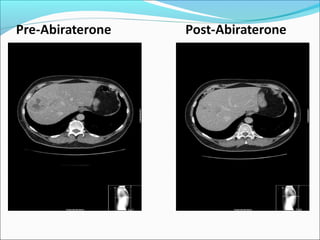

Abiraterone Post-docetaxel Phase II (n=34) 17/34 (50%) pts ≥50% decline 22/34 (65%) pts ≥30%decline 24/34 (71%) pts had a PSA decline 3 pts did not reach 12-weeks but are included

Pre-Abiraterone Post-Abiraterone Massively Enlarge Lymph Node Lymph Node Resolved